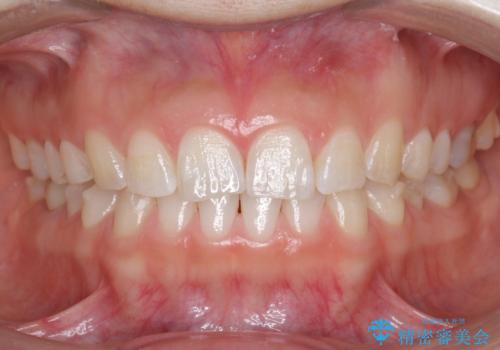

下の前歯のちょっとしたがたつきを治したい

- 下の前歯のがたつきを治したいとのことでした。

上の前歯のちょっとしたねじれも治療しています。

軽度だったため、部分矯正のコースで短期間で治療しました。

下の歯並びを並べるため、わずかに歯を削合しています。

そうしないと、前に出て上の前歯に強く当たってしまうためです。また、後戻りを防ぐ効果もあります。

年齢を重ねてくると、下の前歯が目立つようになるので治療しておくと若々しい印象を保つことができます。